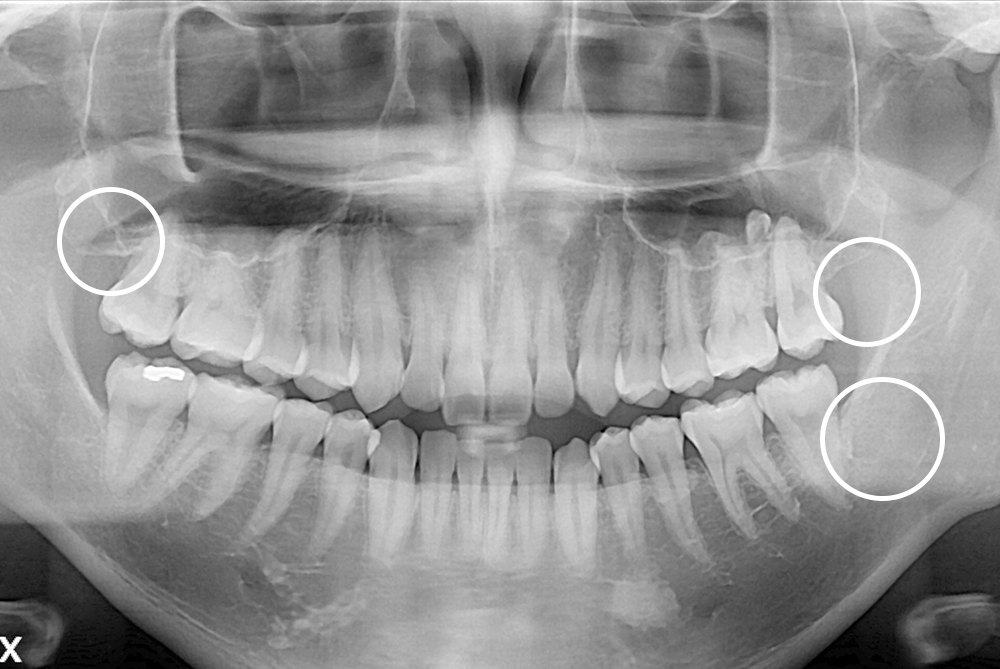

[사랑니] 매복 사랑니 발치

치료전 : 2020-01-06